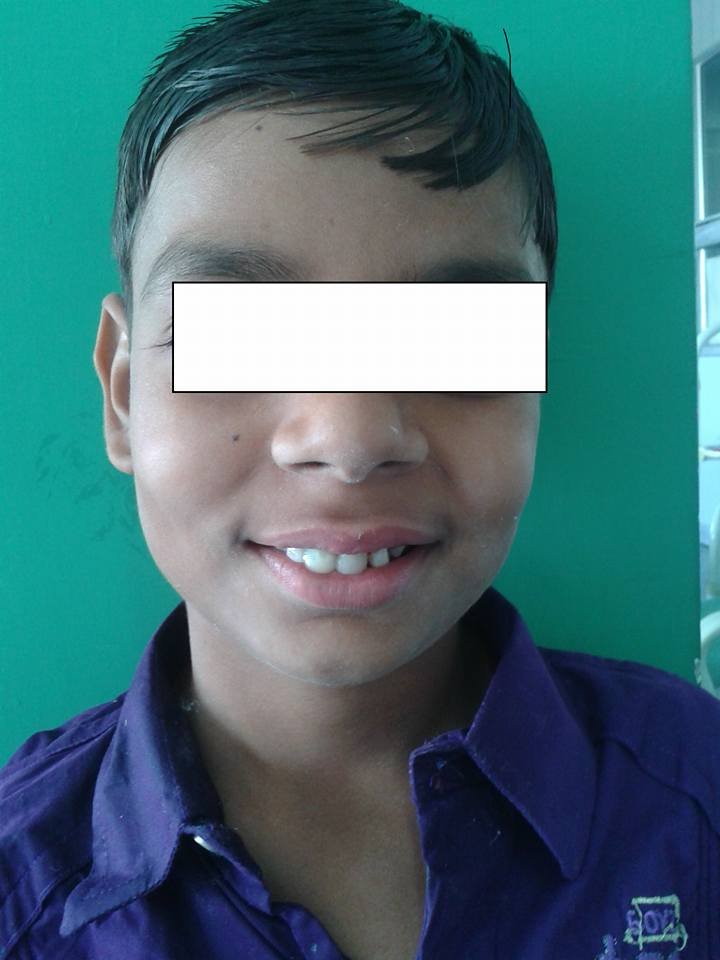

"Step into our world of healthy smiles! At Kreative Dental Care, we believe every smile tells a story. Explore our gallery to see glimpses of our clinic, advanced facilities, happy patients, and memorable moments from events, recognitions, and community initiatives."